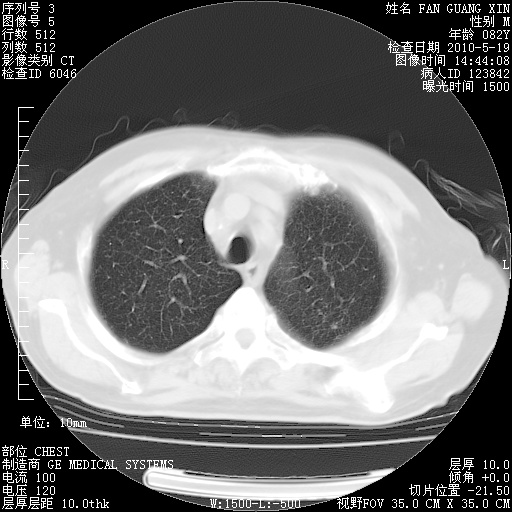

复查肺部CT,明显好转。为什么发热呢?

治疗3周后的肺部CT